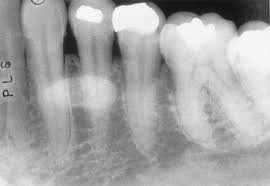

Mandibular canal

Pathway in the bone where the inferior alveolar nerve and blood vessels flow through the mandible.

Extend from mandibular foramen within the ramus to the mental foramen.

Appears radiopaque